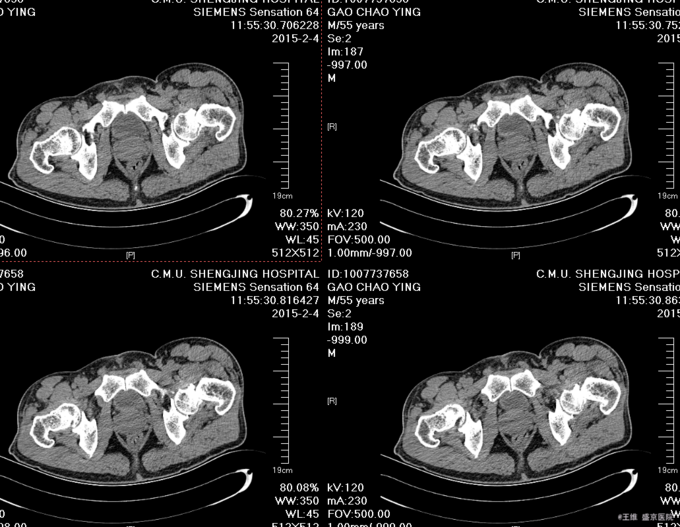

患者自述于2015-12-3日15时在工厂干活时不慎由梯子上摔落(高约3米),致左髋部疼痛、活动受限,不能站立行走,急送至当地医院行骨盆DR示:左股骨颈骨折。现患者为求进一步诊治来我院,急诊以“左股骨颈骨折”为诊断收入我科。患者自受伤以来一般状态可,无发热,无头晕、呕吐,无胸闷、心悸呼吸困难,无腹痛、腹泻,饮食可,睡眠可,二便正常。

患者入院后完善相关检查,查无明显手术禁忌症后,CSEA下行左股骨颈骨折闭合复位空心钉内固定术,术后患者抗炎等对症治疗,患者第二天退院。嘱患者卧床休息3个月后,复查。